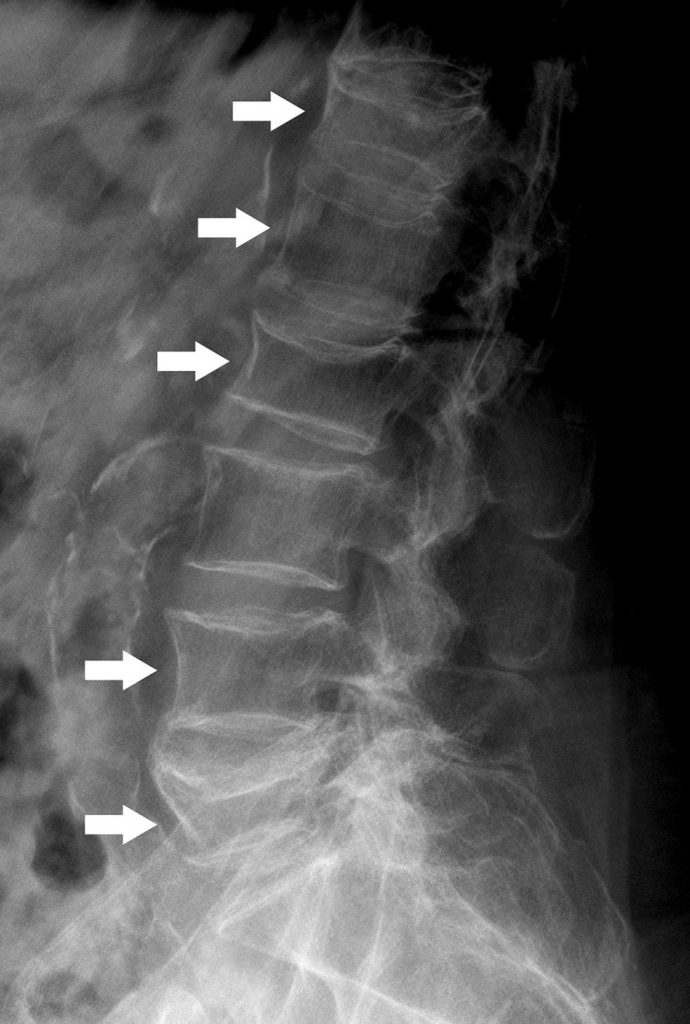

Fig. 83.1 Radiographie (profil) du rachis lombaire.

Déminéralisation diffuse des corps vertébraux. Multiples fractures vertébrales avec perte de parallélisme des plateaux vertébraux (flèches).

Source : CERF, CNEBMN, 2022.

- Les éléments sémiologiques d’une fracture vertébrale sont :

- la perte de parallélisme des plateaux vertébraux (figure 83.1) ; il existe trois types de déformation des corps vertébraux : cunéiforme (diminution de hauteur de la partie antérieure du corps vertébral, le plus souvent au rachis thoracique), concave ou biconcave (fracture de la portion centrale du corps vertébral, le plus souvent au rachis lombaire) ou en galette (perte de hauteur globale du corps vertébral) ;

- la sévérité du tassement selon l’importance de la perte de hauteur vertébrale (grades de sévérité : 15–25 %, 25–40 %, plus de 40 %).